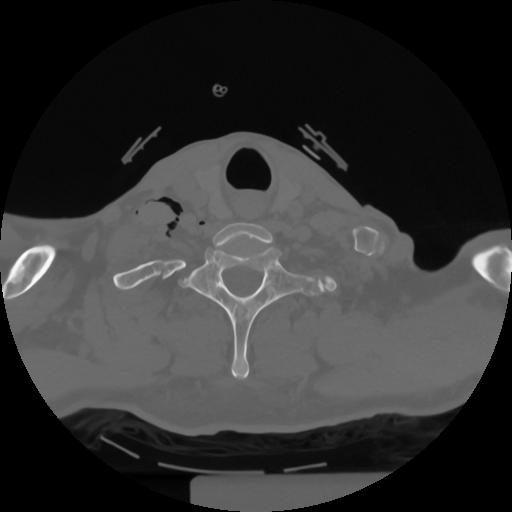

12 P.BLANDAS,,Vol,0.5,P.BLANDAS,,